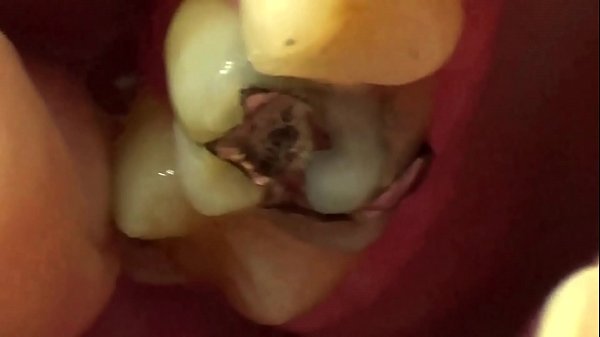

Mouth Tour With FifiFoxx

3 min